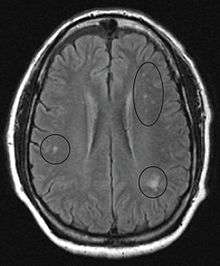

In the brain itself, changes are less severe: They occur as small sources of nervous fibers decay and accumulation of astrocytes, usually subcortically located, and also round hemorrhages with a torus of glial cells. Pathological changes can be noticed as well in the posterior roots of the cord and, to lesser extent, in peripheral nerves. Abnormalities might be observed in MRI.[41]